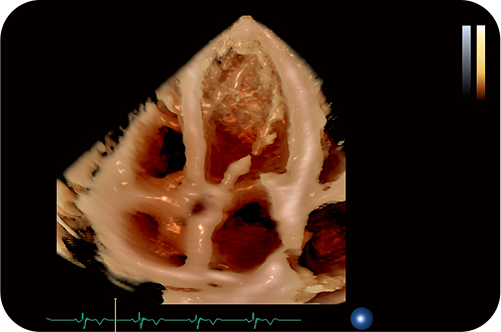

УЗИ система последнего поколения #2

Топовая 4D-визуализация сердца — легко использовать в повседневной практике врача-диагноста